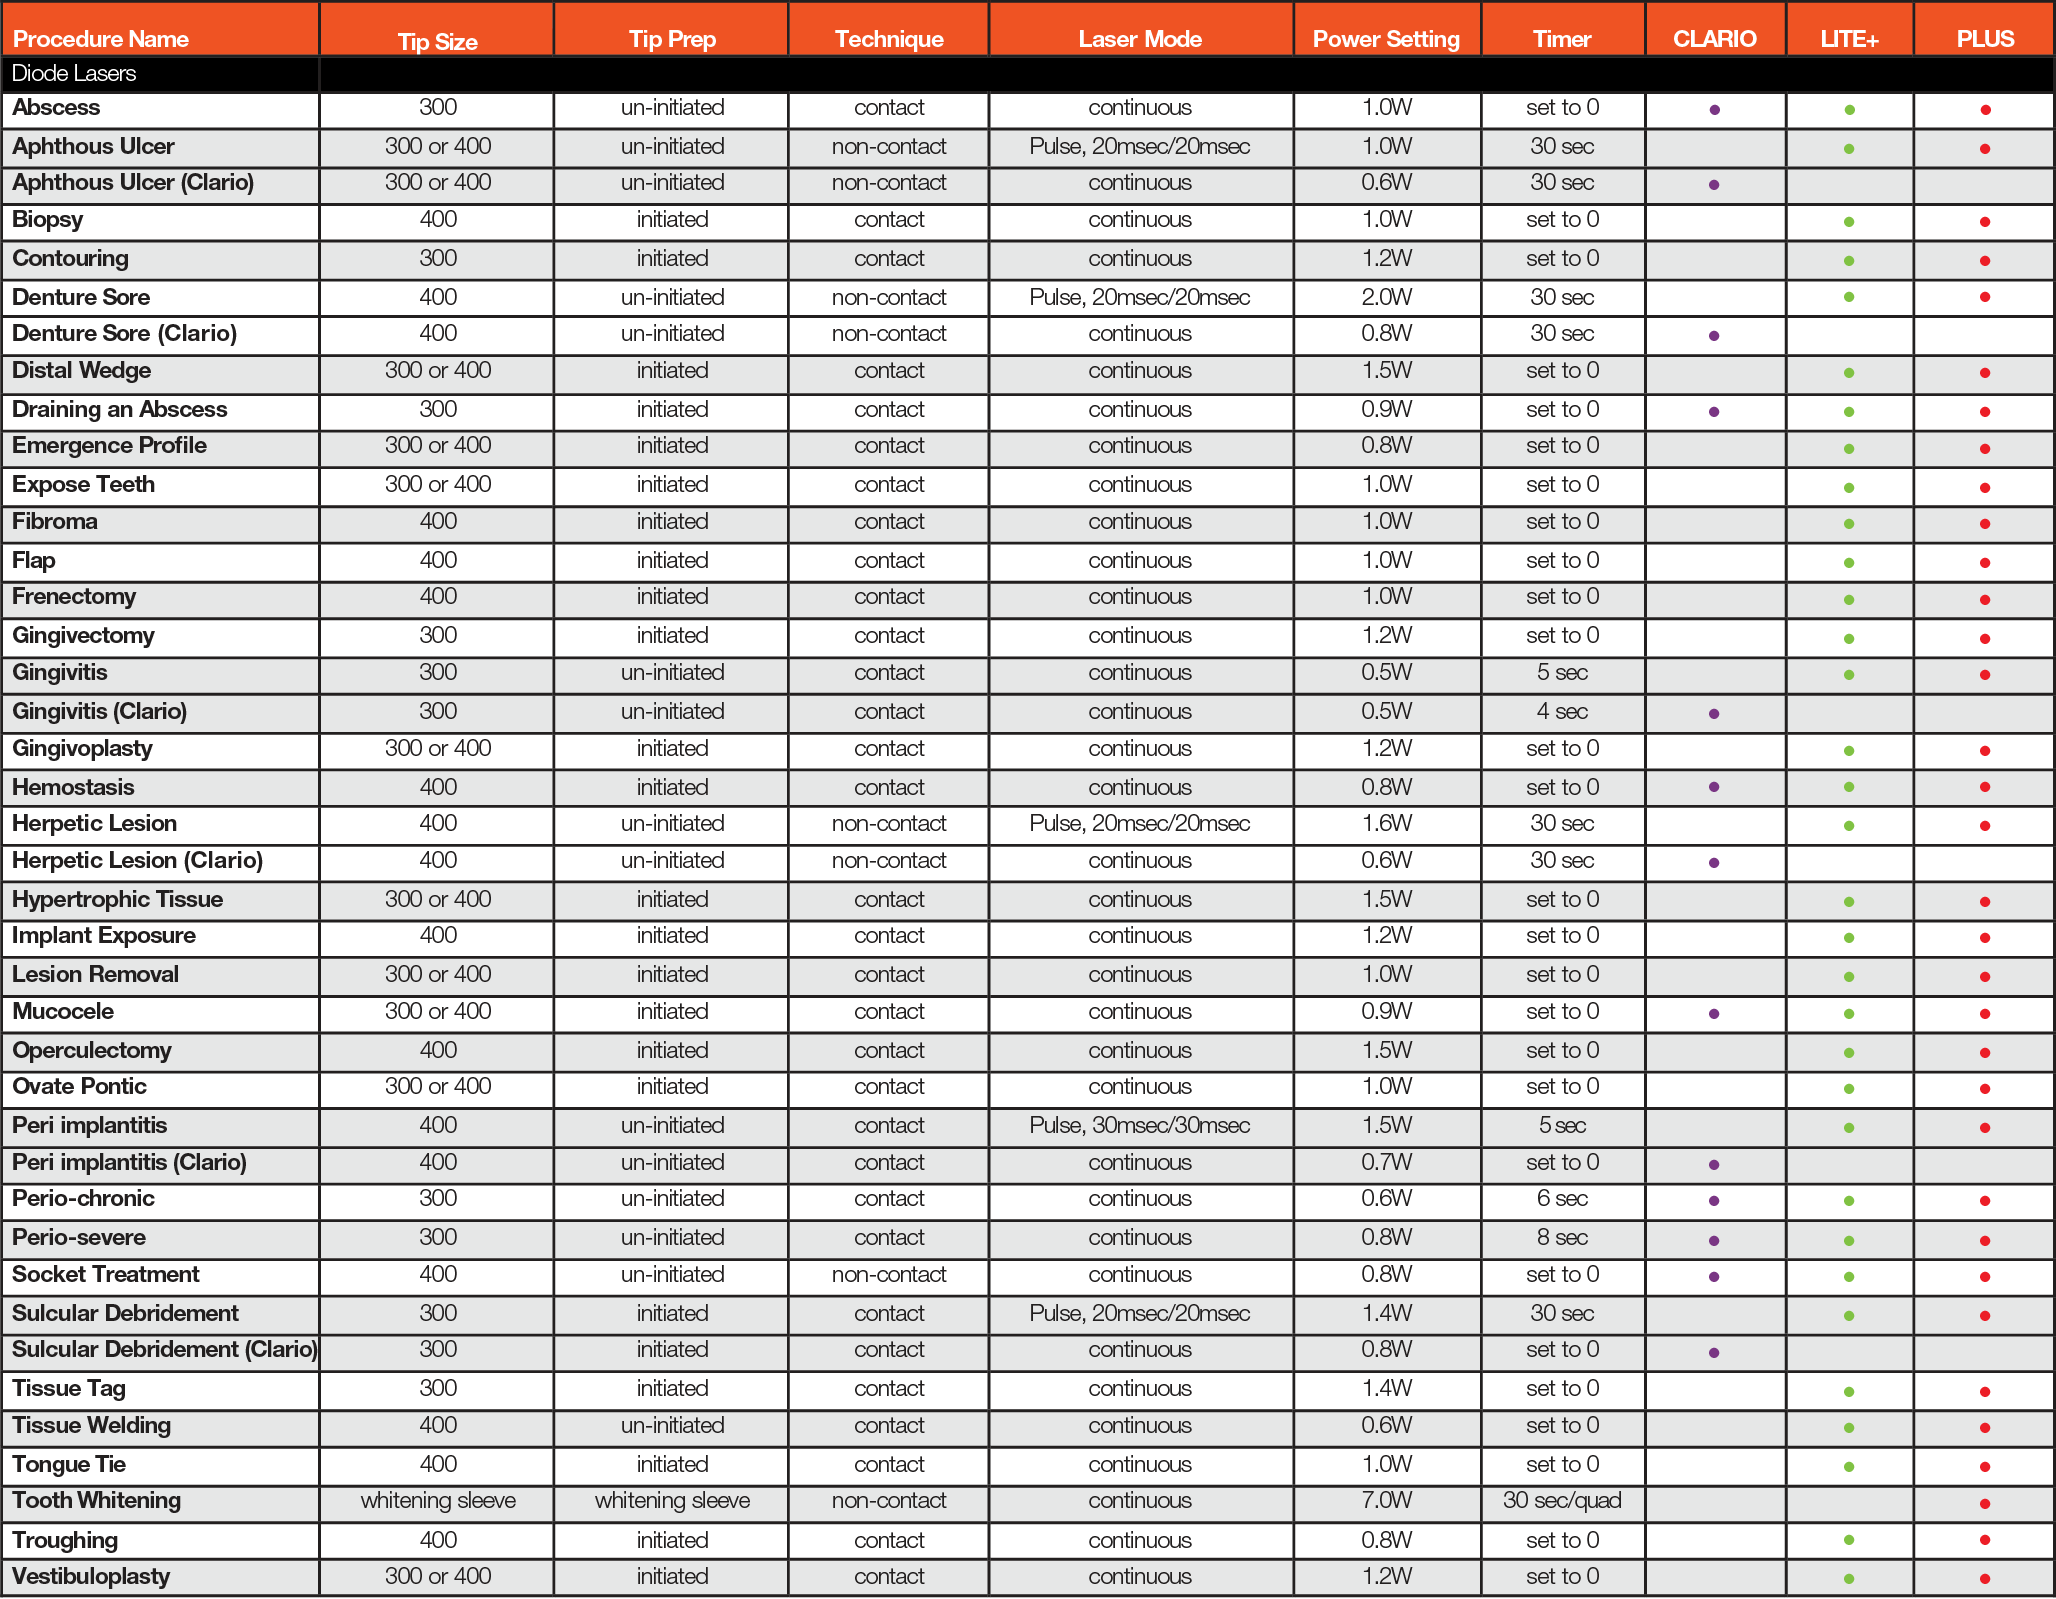

MORE VERSATILITY MEANS MORE REVENUE

Specifically customized for a hygienist’s unique job requirements, the Picasso Clario Diode Laser can perform up to 21 different periodontal and soft-tissue laser procedures with a focus on bacterial reductions, soft-tissue treatments, and laser hygiene therapies—allowing your dental practice to expand its services. Treat gingivitis, herpetic lesions, and more*--and never outsource soft-tissue and hygiene laser procedures again.

* See procedure chart below for a complete list

The Picasso Clario Laser is pre-programmed with 5 special modes, making it a complementary choice for both beginner and expert laser practitioners. Modes such as Gingivitis-Mode are particularly designed for the treatment of inflammation while the trademark Picasso Laser Perio-Mode is ideal for laser-assisted periodontal therapies and laser bacterial reduction. Whether it’s a mild case of gingivitis or severe periodontitis, the Clario has the tools for any dental hygiene procedure.

MODES CHART